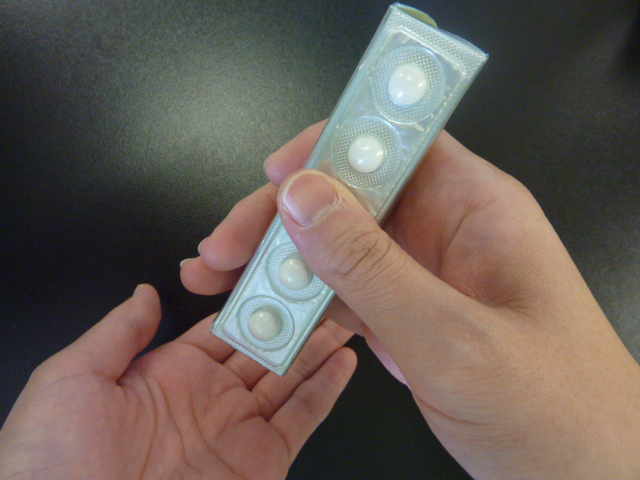

高齢者に多い事故 薬の包装シート Ptp 誤飲 はなぜ怖いのか

お薬の小児誤飲防止パッケージ スライド台紙ptp 株式会社カナエ

薬のptpシートを1錠ずつバラバラにするのは止めて下さい 第4報

ptp包装シートの誤飲 平成23年4月 日本薬剤師会 Ppt Download

薬のptp包装の誤飲 高橋ペットクリニック 福岡県春日市の犬猫動物病院

高齢者の誤飲食で最も多い 薬の包装の誤飲 に注意しましょう Rme

のどや食道を傷つけることも 薬の包装シートの誤飲に注意 萩市

包装シートの誤飲 はな薬局 宮崎市にある調剤薬局のはな薬局です